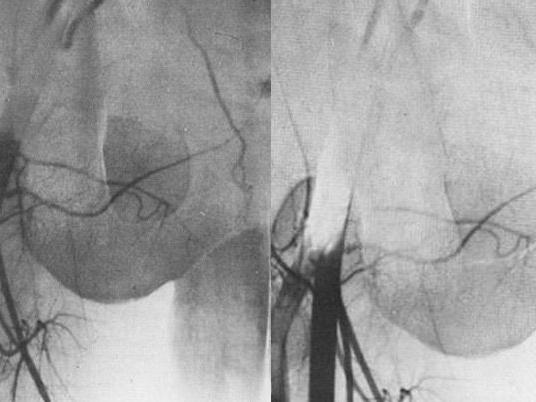

Balkan ülkesi Sırbistan'da testisleri olmadan dünyaya gelen bir adama tek yumurta ikizinden alınan testis nakledildi. Uluslararası bir cerrah ekibinin başkent Belgrad'da geçen salı günü gerçekleştirdiği ameliyat, 36 yaşında olduğu belirtilen adamın çocuk sahibi olabilmesini sağlayabilir.

Doktorlar, altı saat süren nakil ameliyatına giren Sırp kardeşlerin durumlarının iyi olduğunu, alıcının testosteron seviyesinin normale ulaştığını açıkladı. Ayrıca donör kardeşin çocuğunun bulunduğu ve üreme kabiliyetinde herhangi bir eksikliğin olmayacağı belirtildi.